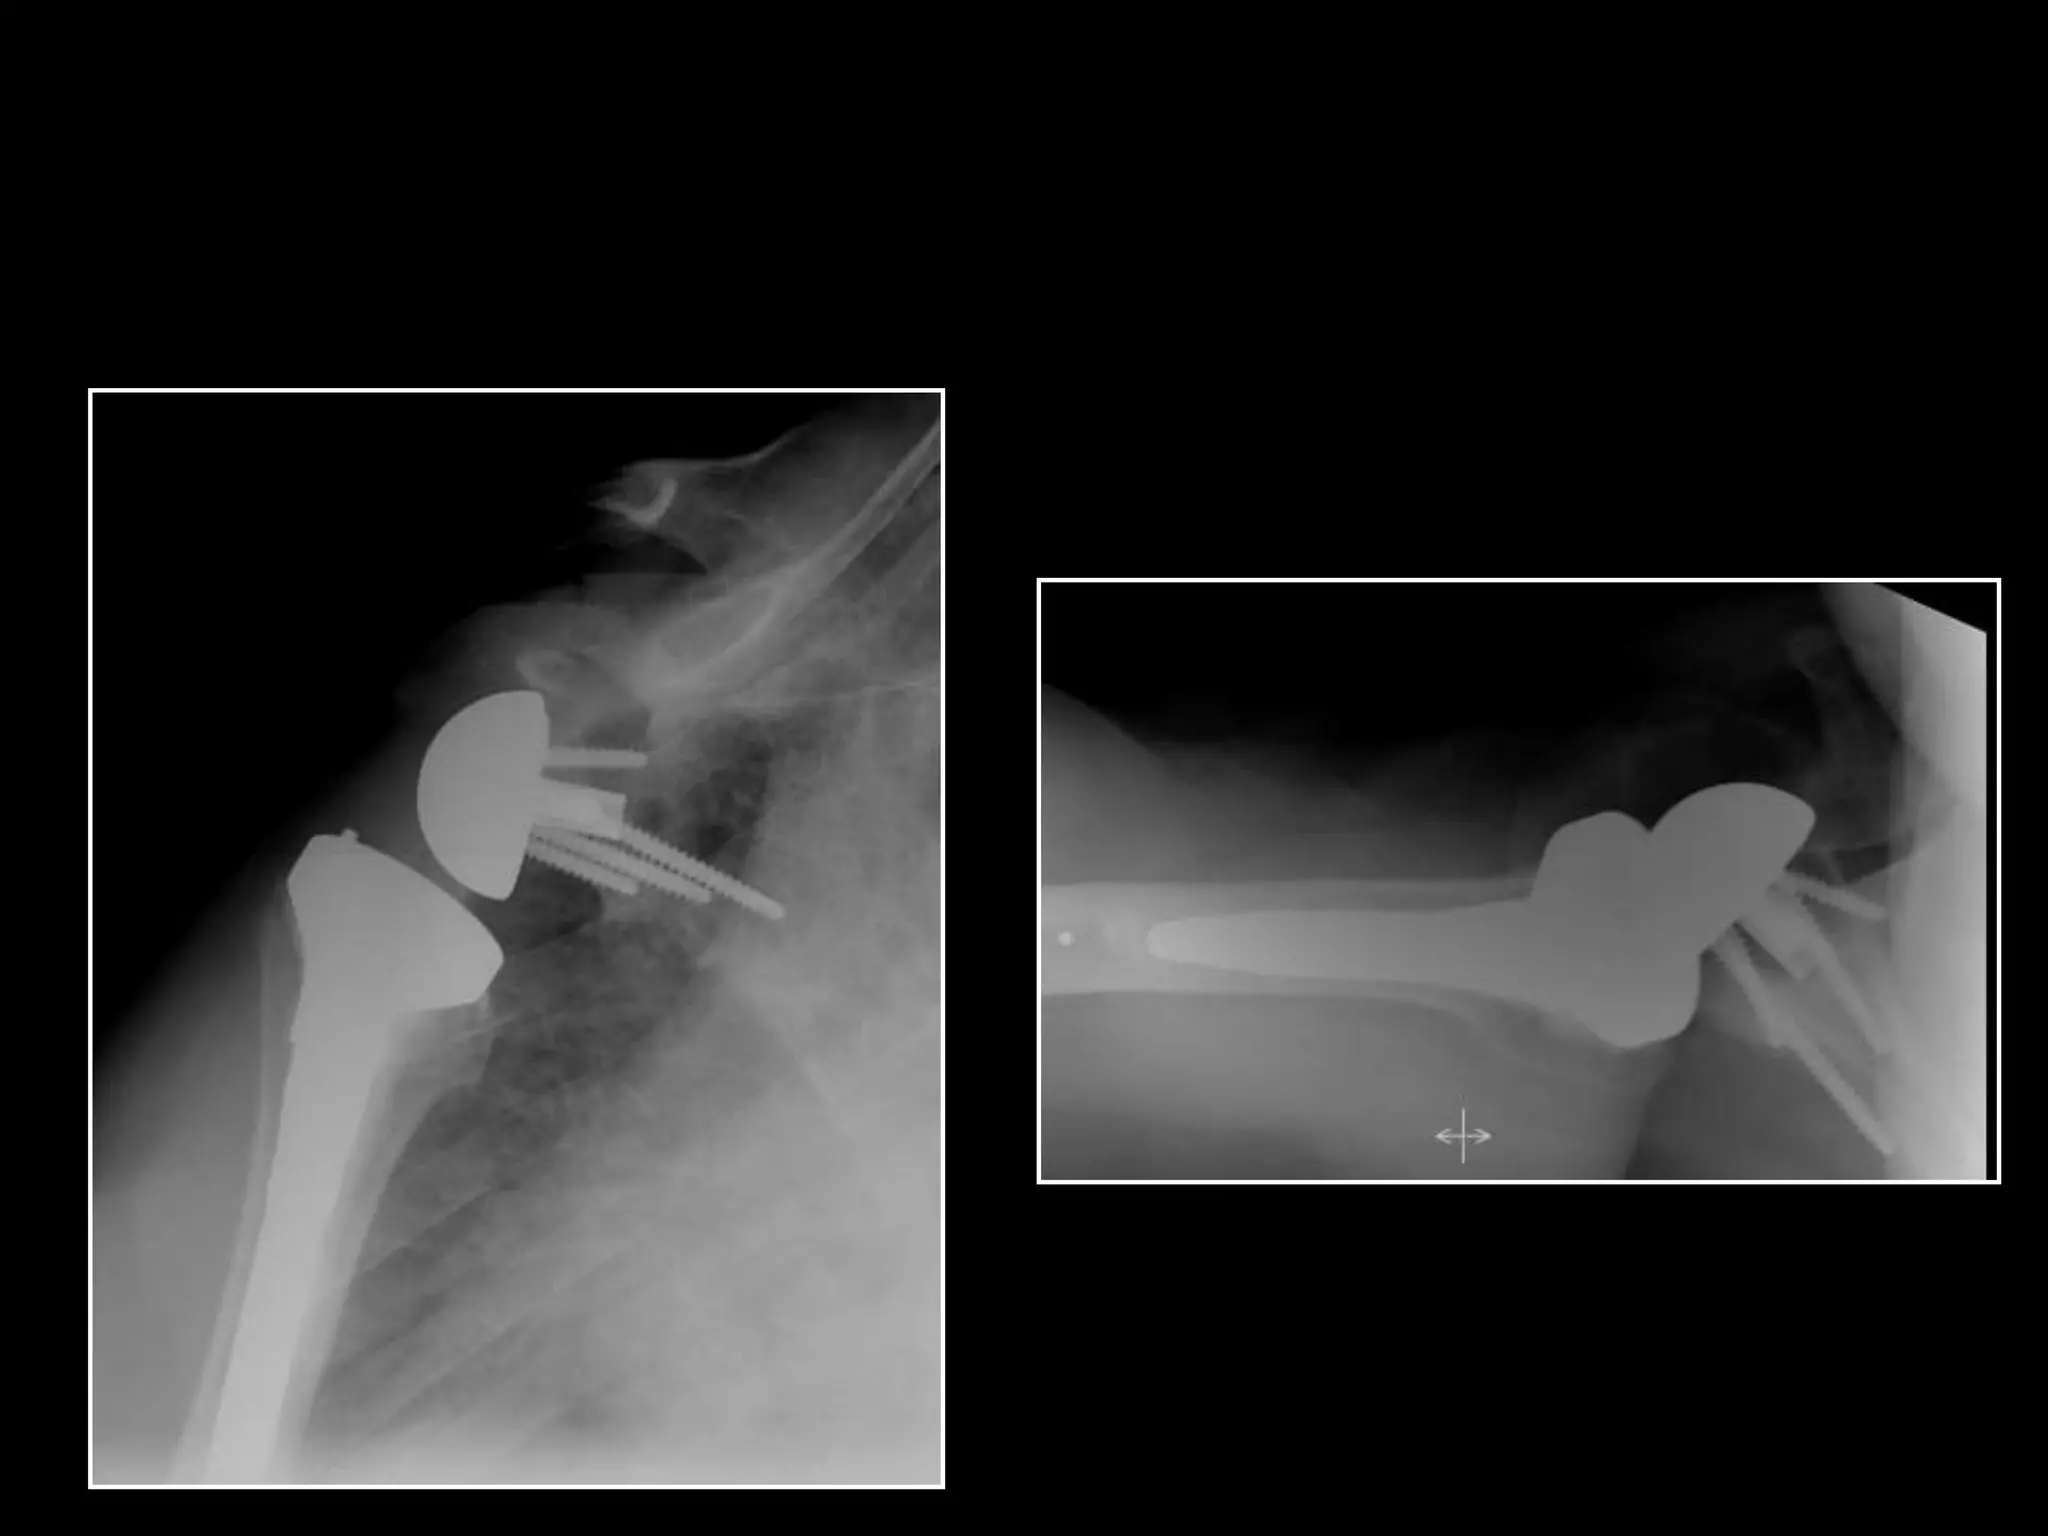

SURGICAL TECHNIQUE

MADRID